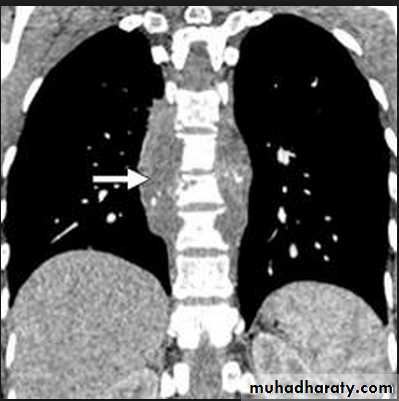

Nodular (coin) lesion in the left upper lung with irregular edge (most probably cancinoma